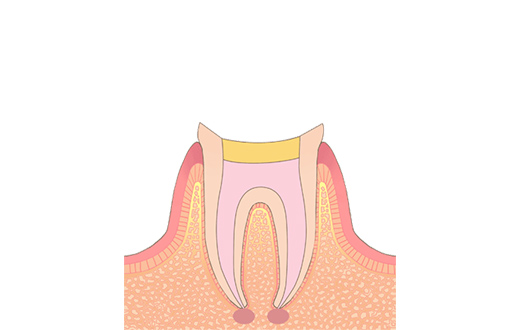

C1初期う蝕

一般的に初期むし歯と言われています。ごく浅い、エナメル質という歯の一番外側に限局した虫歯です。機能や審美的に問題がなく、虫歯の進行が認められなければ、治療は必要ありません。初期むし歯になってしまった部分は虫歯が進行しやすいため、より丁寧なブラッシングが必要になります。